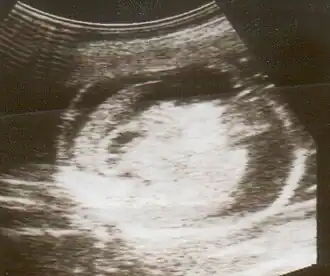

Uma ultrassonografia mostrando um feto com hidropisia fetal.

Hidropisia fetal pode ser diagnosticada e monitorada por ultrassom. O exame Pré-natal e a ultrassonografia permitem a identificação precoce de hidropisia fetal.